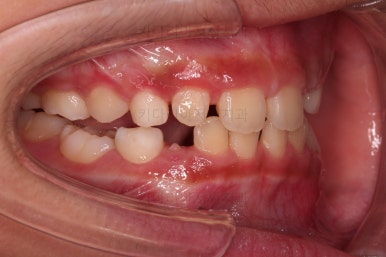

마찬가지로 초진시의 입안 모습입니다.

보호자분 말씀처럼 윗니가 아랫니에 비해서 나와보이는게 사실이네요.

그럼 정말 윗니가 튀어나온게 맞을까요?

이번 환자분의 경우 골격 자체가 위턱(코주위~윗니부분을 아우르는 골격)이 약간 앞으로 발달하고 아래턱이 성장이 모자라 뒤로 들어간 상태였어요.

따라서 상대적으로 위턱이 크고 상대적으로 아래턱이 작았던거죠.

이런 부조화된 모습때문에 입을 어색하게 다물게 하고 입을 튀어나와 보이게 만드는거였어요.

특히 아래턱이 작을 경우 거의 필연적으로 생기는 과개교합(아래 앞니가 윗니에 매우 많이 가려져 있는 증상)도 상당히 많이 개선이 됩니다.